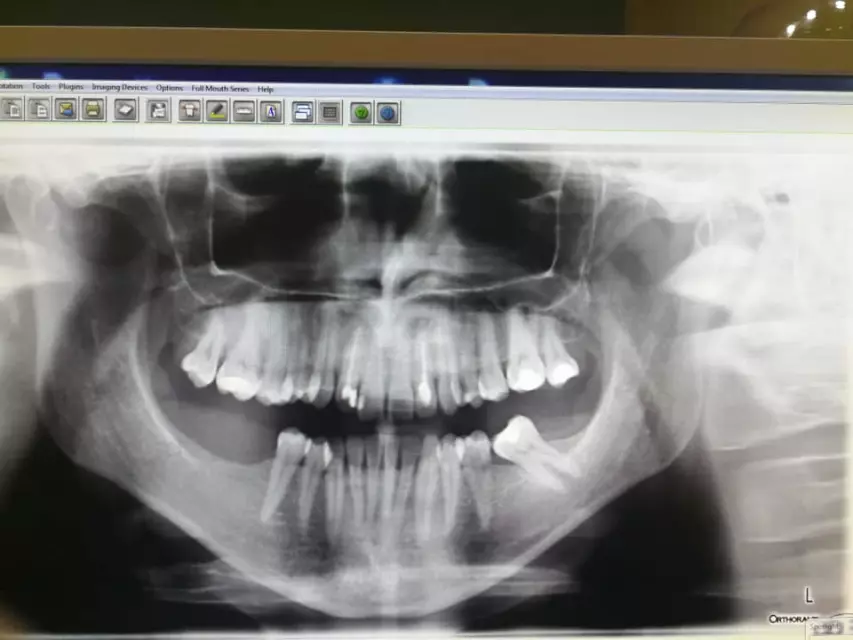

Ovaj zubar vrši različite postupke, poput popravka zuba, uklanjanja zubnog kamenca, liječenja zubnog mesa i zubne pulpe te postavljanja protetskih nadomjestaka.